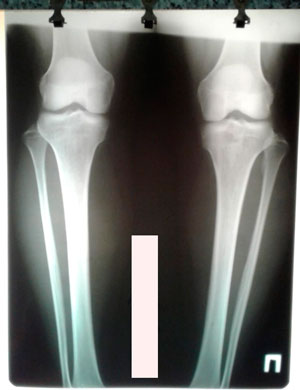

Re: ♥Марина♥

Сообщение Sekretar Onipko »

перед крутками

Вложения

IMG_7159-18-11-19-07-51.JPG